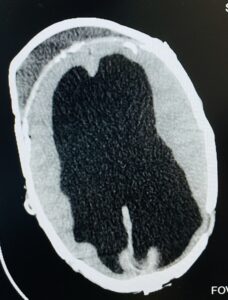

Figure 3: CT scan of brain (axial view) obtained in 2023 May, after shunt removal and awaiting further surgery

A posterior vault reduction was performed through a coronal parieto-occipital approach with mesh fixation. Follow-up imaging revealed dual calvaria formation, with new ossified bone developing along the dura and a fluid plane separating it from the outer cranial vault.

The dura mater is osteogenic; it orchestrates calvarial morphogenesis by secreting growth factors and recruiting osteoprogenitors. After dural release/reconstruction, intramembranous ossification over the dura can create an inner neocalvaria, clinically visualized as a “dual skull” with a fluid plane (hydroma) between inner and outer tables, as in our patient. This phenomenon is well documented experimentally and clinically.